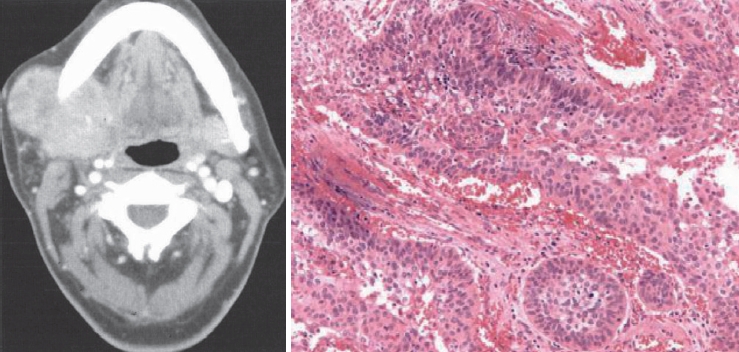

문 1. 30세 여자 환자가 1년 전에 발견한 우측 귀 밑 종물을 주소로 내원하였다. 외래에서 시행한 전산화단층촬영 소견은 다음과 같다. 이 환자에게 수술을 시행한 후 얻은 검체에 대한 병기 소견이다. 이에 대한 설명 중 옮은 것은?

① 이하선에 발생한 양성 종양이기 때문에 수술을 통해 완치되며 추가적인 치료는 필요 없다.

② 타액선 암종의 치료에서는 안면신경 등 중요한 구조물이 많기 때문에 수술 후 안면신경마비 가능성을 설명하고 신경 침범이 의심되는 경우 신경 이식술을 고려한다.

③ 타액선 암종은 방사선 치료와 항암 치료에 반응이 좋기 때문에 주위조직 침범이 의심되면 제거하지 않고 방사선 치료를 병행한다.

④ 타액선 암종은 조직학적 등급에 상관없이 림프절 전이가 드물기 때문에 수술 전 영상검사에서 림프절 전이가 의심되지 않으면 예방적 경부 림프절 절제술을 시행할 필요가 없다.

⑤ 타액선 암종의 수술 범위는 악성도가 높은 경우 이하선 천엽 절제술만으로 충분하다.

문 1. 답 ②

해 설 참고 문헌: 대한이비인후과학회. 이비인후과학:두경부. 파주: 군자출판사;2018. p.359-73.